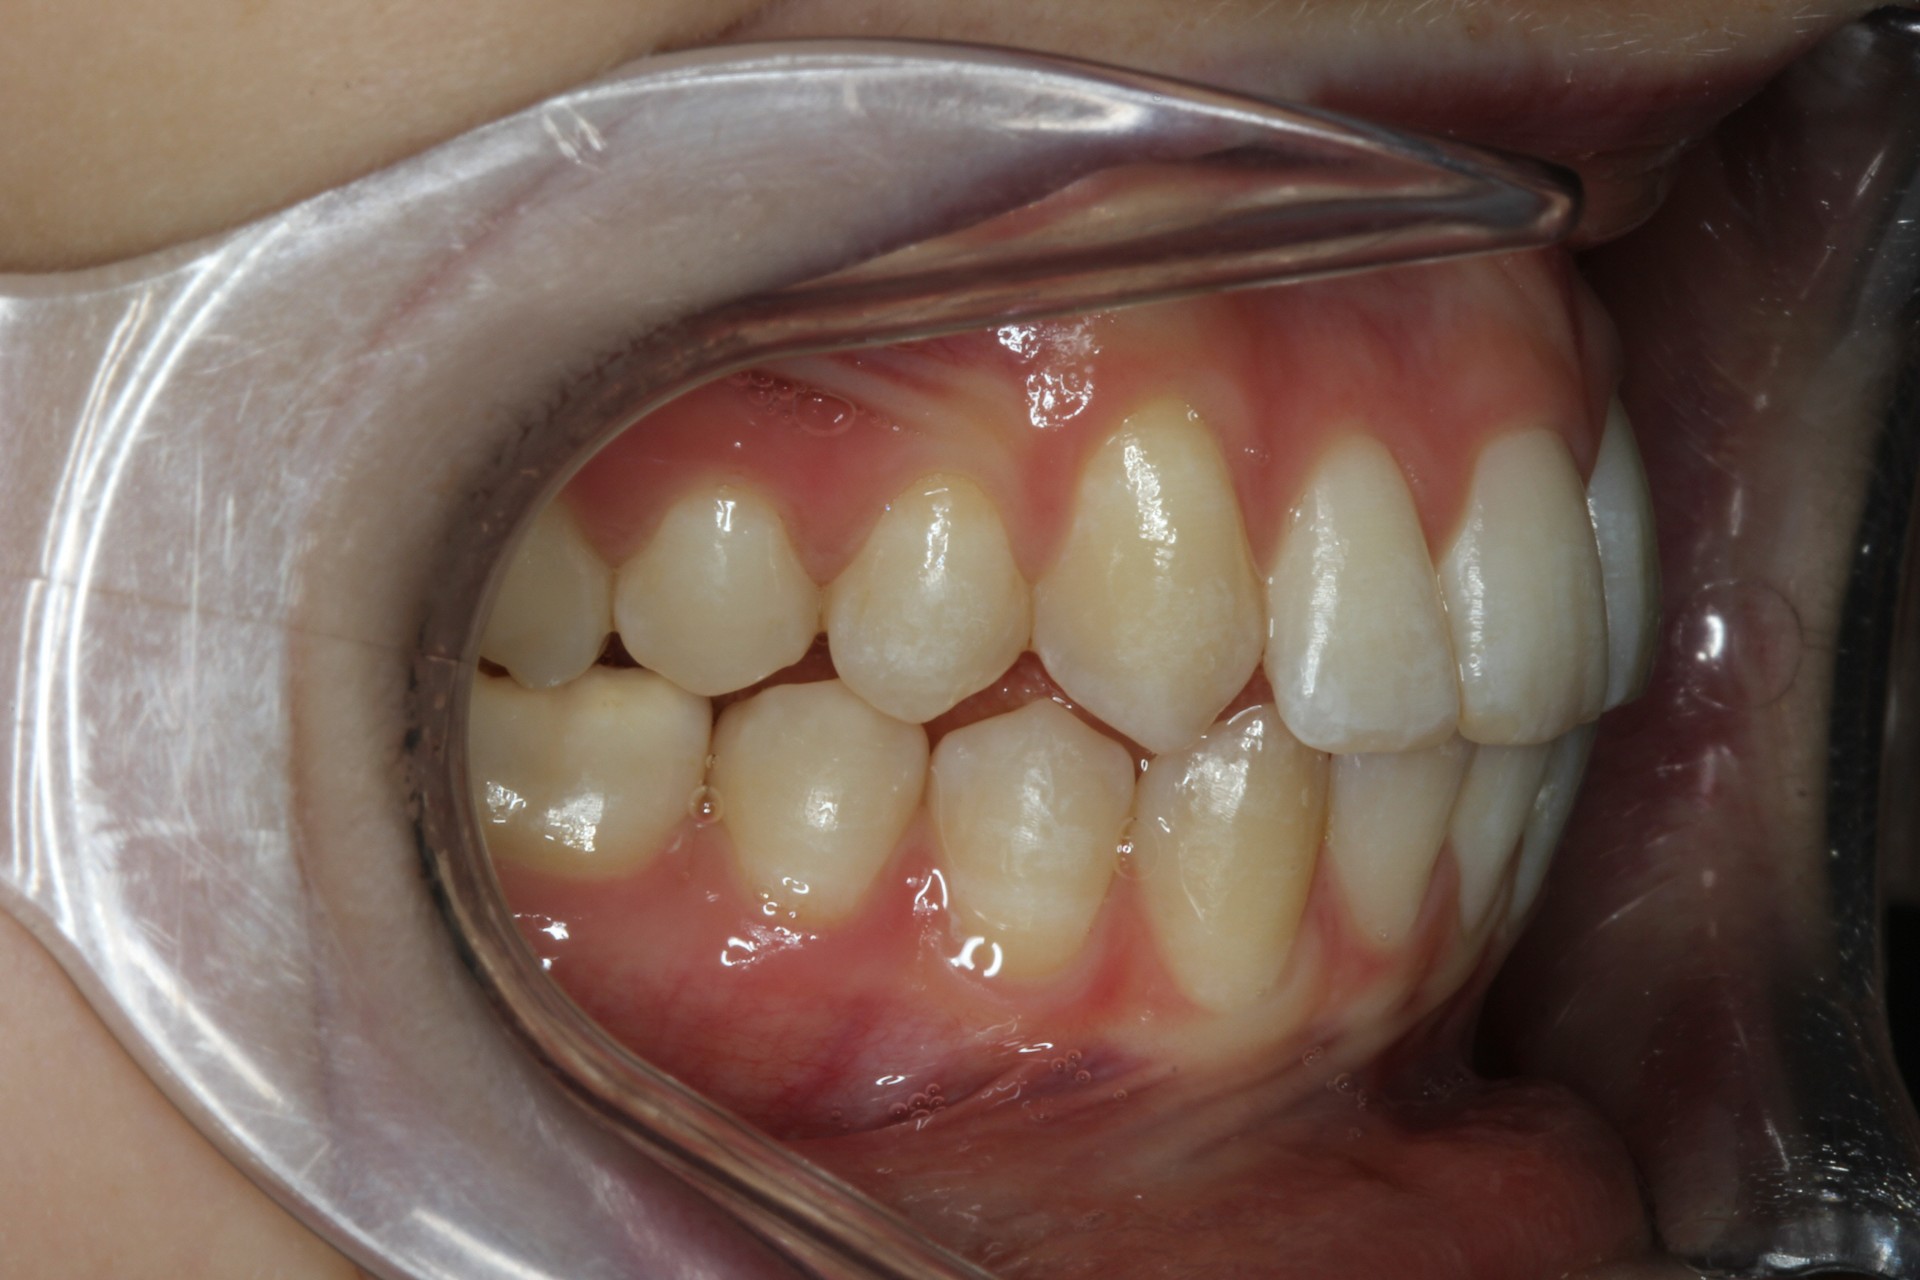

Protruding front teeth – Child case